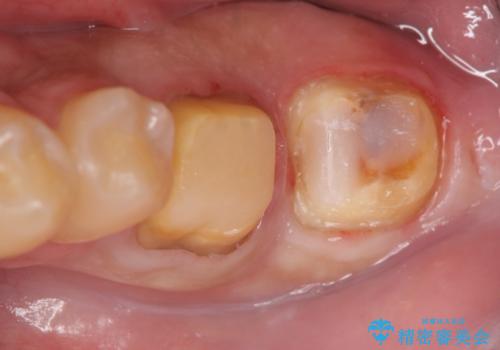

- 左下7の歯しみる、被せ物を被せてもすぐに外れてしまうといらっしゃった方の症例です。

左下に被せ物を被せるクリアランス(補綴のための上下のスペース)ないため、十分な歯冠長を確保するため歯冠長延長術を行いました。

その後歯肉の回復を待ち、フルジルコニアクラウンにて補綴を行いました。